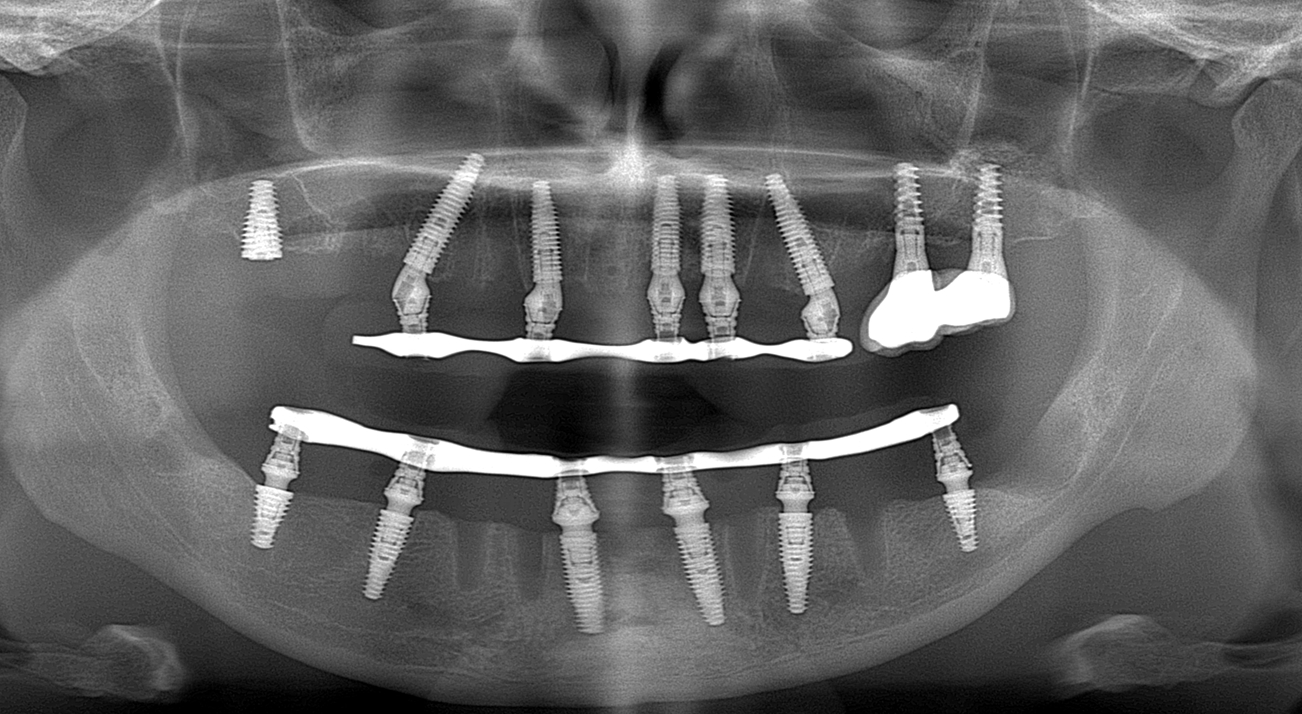

ПроблемаХронічний генералізований парадонтит 2-3 ст тяжкості

РішенняІмпалнатція по системі All on 6 NeoDent та установка композитних протезів на титанових балках

Термін лікування4 месяца